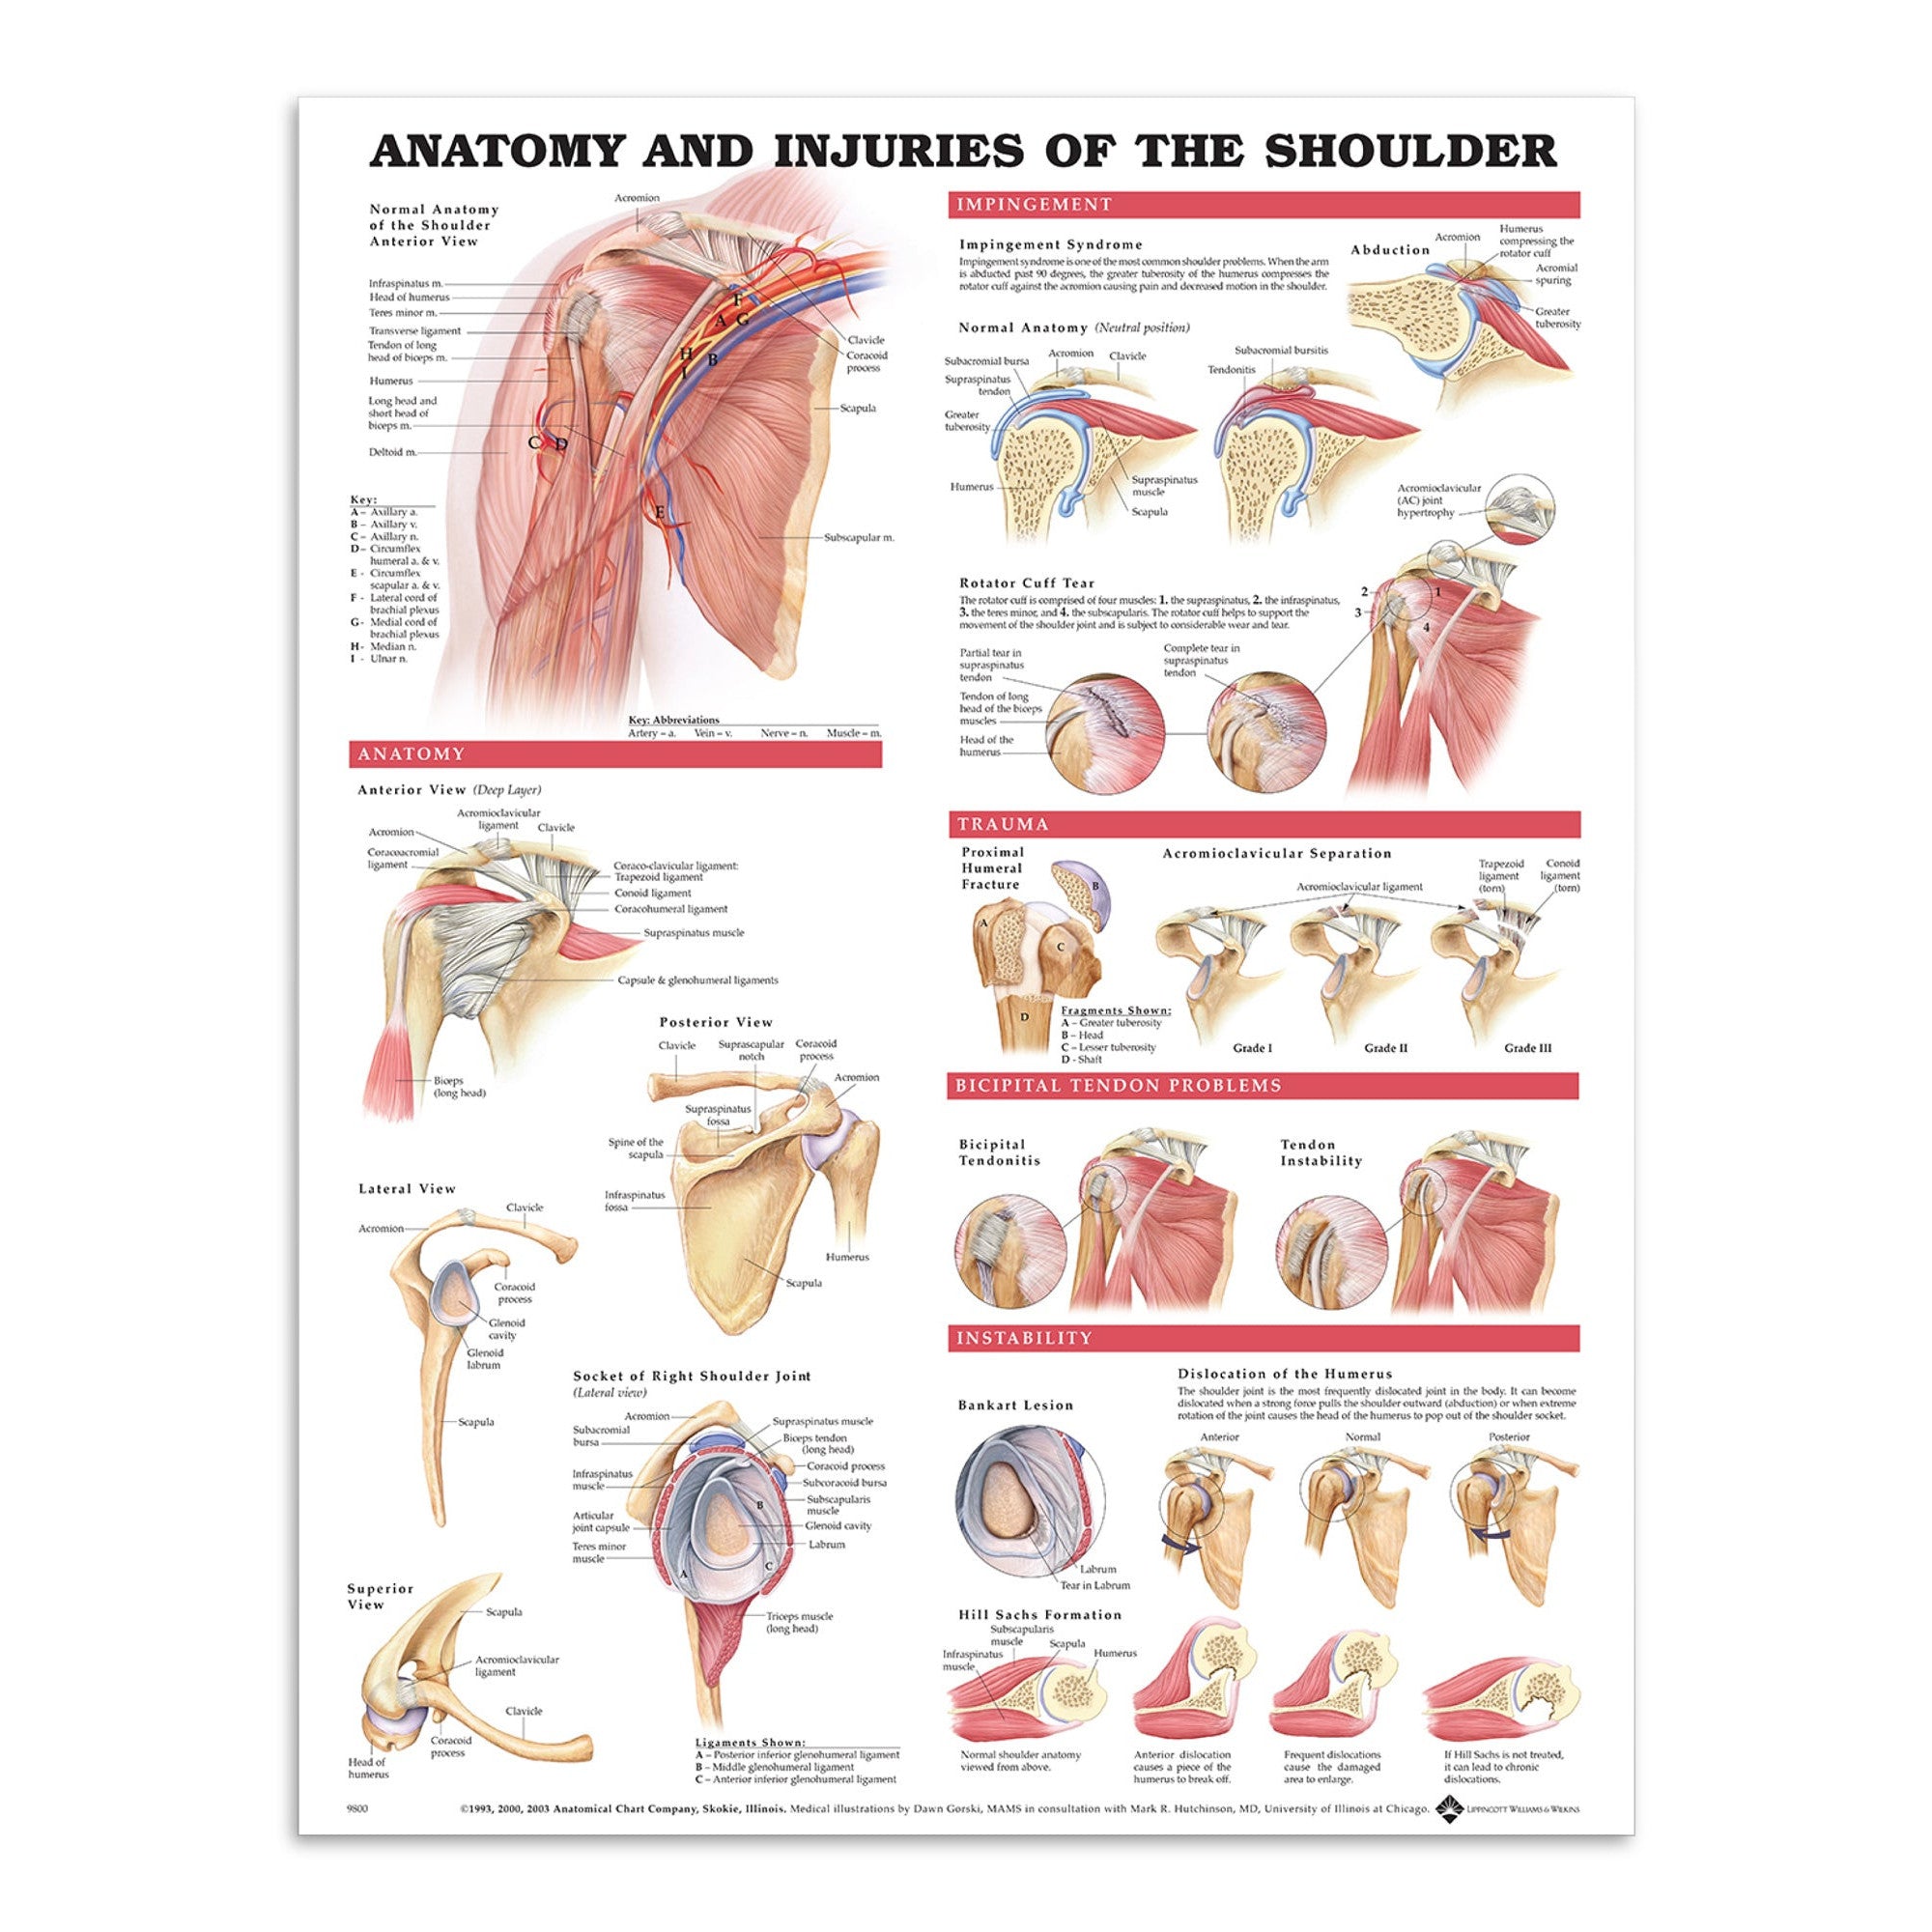

Muscle posters

Muscles provide movement to the musculoskeletal system, and their origins, insertions and lodges are clinically important for every healthcare professional. That is why we at eAnatomi have both developed and designed our own anatomy posters, which provide the ultimate overview of all the muscles of the body. On this page you can find both our own posters and posters from other manufacturers. We offer posters in several different languages such as pure Latin, Danish, English and Swedish, etc.